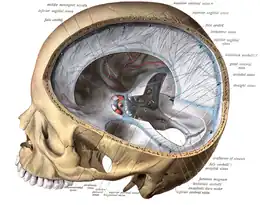

Pathogenesis

The veins of the brain, both the superficial veins and the deep venous system, empty into the dural venous sinuses, which carry blood back to the jugular vein and thence to the heart. In cerebral venous thrombosis, blood clots usually form both in the veins of the brain and the venous sinuses. The thrombosis of the veins themselves causes venous infarction (damage to brain tissue due to a congested and therefore insufficient blood supply). This results in cerebral edema (both vasogenic and cytotoxic edema), and leads to small petechial haemorrhages that may merge into large haematomas. Thrombosis of the sinuses is the main mechanism behind the increase in intracranial pressure due to decreased resorption of cerebrospinal fluid (CSF). The condition does not typically lead to hydrocephalus, however, because there is no difference in pressure between various parts of the brain.[3] However, those who have deep cerebral venous sinus thrombosis or oedema at basal ganglia are more prone to hydrocephalus development.[13]